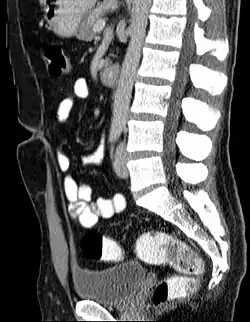

Unterbleibt die Rückbildung entsteht eine Urachusfistel, bei teilweiser Rückbildung ein Urachusdivertikel oder eine Urachuszyste.